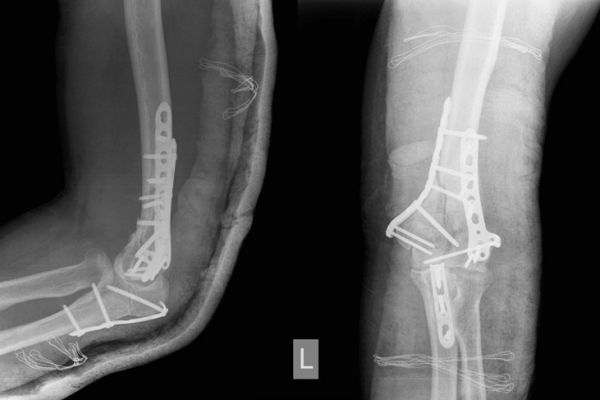

Gabinet ortopedyczny prowadzony przeze mnie specjalizuje się w leczeniu schorzeń i urazów kończyn górnych i dolnych. Zajmuję się leczeniem choroby zwyrodnieniowej stawu biodrowego i kolanowego, uszkodzeń wewnętrznych stawu kolanowego i barkowego, złamań w obrębie kończyn górnych i dolnych oraz urazów ścięgien i mięśni kończyn górnych i dolnych. Ponadto wykonuję diagnostykę USG narządu ruchu i badanie preluksacyjne (USG bioderek niemowląt). Leczę również neuropatie uciskowe kończyn (zespół kanału nadgarstka, rowka nerwu łokciowego, kanału Guyona) oraz uszkodzenia wewnętrzne stawów kończyn górnych i dolnych. Zapraszam do mojego gabinetu, gdzie dobiorę odpowiednie do schorzenia metody leczenia i zakwalifikuję do ewentualnego leczenia operacyjnego. W celu umówienia się na wizytę proszę o kontakt telefoniczny z rejestracją gabinetu ortopedycznego w Lesznie.